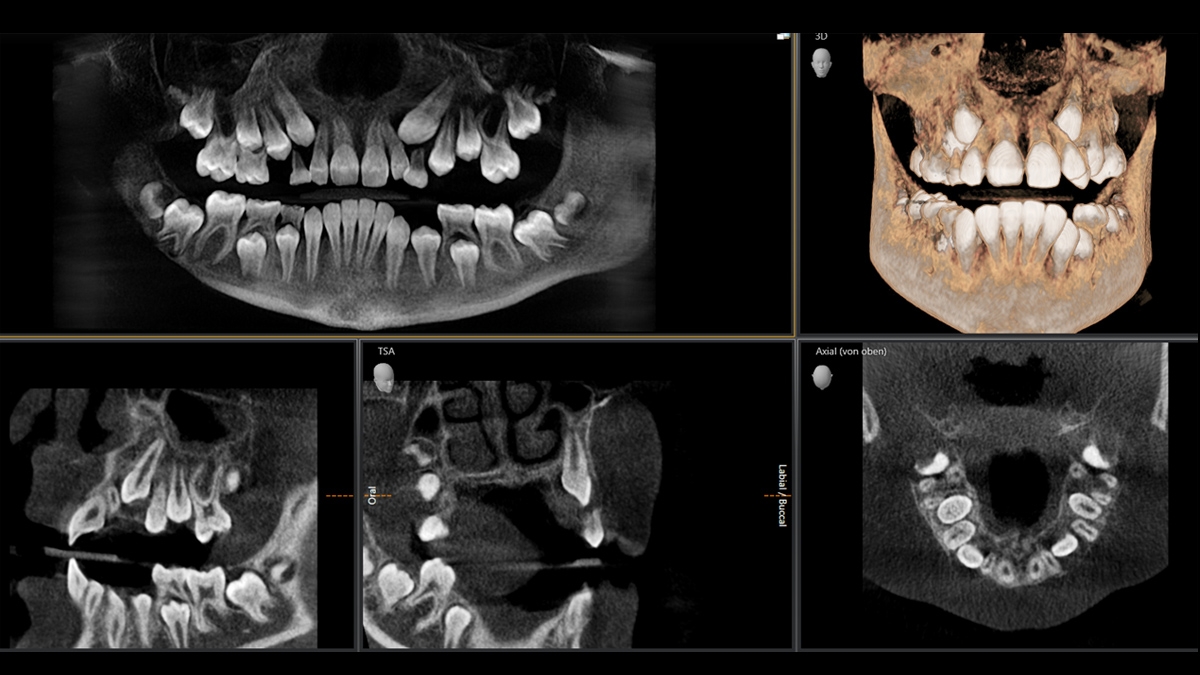

Exemplary 3D Images

Volume Ø 8 x 8 cm Low Dose

3D Low Dose Indication Examples

Indication: Determining the position of teeth. CBCT Volume: Ø 8 cm x 8 cm at 8 μSv